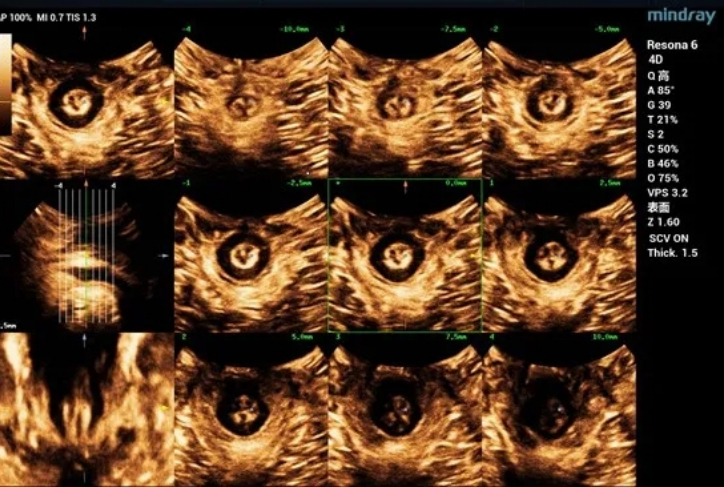

The bladder neck is located 21.2mm above the pubic symphysis at rest, the uterus is located 27.0mm above, and the rectum is located 10.8mm above (see Figure 1).

Figure 1 Two-dimensional ultrasonic measurement of pelvic floor structural parameters at rest

Obvious cystocele, increased mobility of bladder neck, increased urethral rotation angle, increased area of levator ani hiatus (see Figure 6 and Figure 7).

Figure 6 Tomography indicated continuous bilateral levator ani

Figure 7 Tomography indicated continuous internal andexternal sphincter of anus